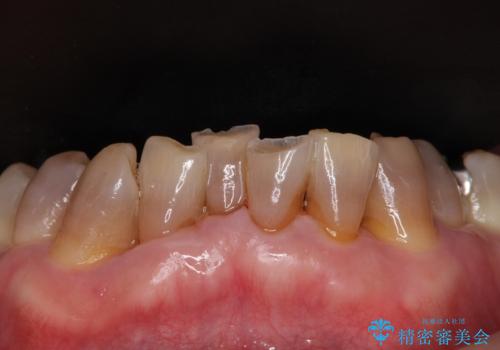

上下ともに前歯のセラミッククラウンによる補綴治療を希望されていましたが、下顎前歯は叢生が強いため、補綴治療前に部分矯正を行って歯列を整えた上で、補綴治療を行うこととしました。

臼歯部には歯周ポケットのある箇所が散見されましたが、まずは前歯を治療したいとのことで、治療を進めました。

ディープバイトにより臼歯部に負担のかかる咬合であったので、補綴治療後には、矯正治療の後戻り防止もかねて、睡眠時にマウスピースを装着するように指示しました。